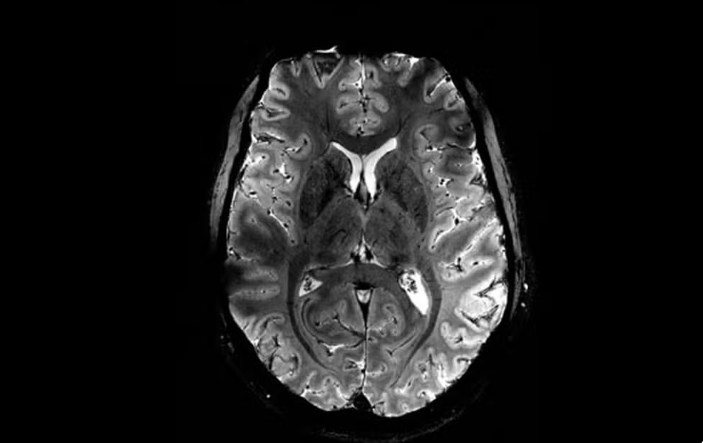

Imagem do Iseult com um campo magnético de 11,7 teslas. — Foto: Reprodução/Comissão de Energia Atômica da França (CEA)

A Comissão de Energia Atômica da França (CEA) divulgou nesta terça-feira (2) as primeiras imagens do cérebro humano feitas pelo aparelho de ressonância magnética mais potente do mundo. De acordo com os responsáveis pelo projeto, o scanner atingiu um nível de precisão jamais visto, algo que pode ser decisivo para detectar doenças.

O campo magnético criado pelo scanner é de 11,7 teslas. Essa potência permite que a máquina escaneie imagens 10 vezes mais precisas do que os aparelhos normalmente utilizados em hospitais – cuja potência geralmente não supera os três teslas.

Em uma tela de computador, Vignaud comparou imagens tiradas por esse poderoso scanner, apelidado de Iseult, com imagens de uma ressonância magnética normal.

“Com essa máquina podemos ver os pequenos vasos que alimentam o córtex cerebral, ou detalhes do cérebro que eram quase invisíveis até agora”, detalha.

Um dos principais objetivos do projeto é aprofundar a compreensão da anatomia do cérebro e entender quais áreas são ativadas quando se realiza determinadas tarefas.

Os cientistas já utilizaram os scanners de ressonância magnética para demonstrar que quando o cérebro reconhece coisas particulares, como rostos, lugares ou palavras, duas regiões do córtex cerebral são ativadas.

A potência de 11,7 teslas ajudará o Iseult a “compreender melhor a relação entre a estrutura do cérebro e as funções cognitivas, por exemplo, quando lemos um livro ou realizamos um cálculo mental”, disse Nicolas Boulant, diretor científico do projeto.